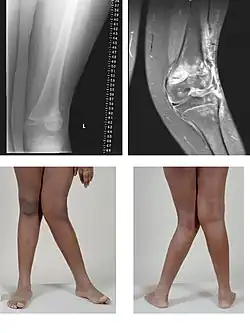

Genu valgum

Le genu valgum (dit également « genou cagneux » ou « genou en X ») est une déviation vers l'extérieur de l'axe du membre inférieur avec saillie du genou en dedans : les deux genoux se touchent alors que les chevilles sont écartées.

Est considéré comme anormal un genu valgum asymétrique ou unilatéral, un genu valgum continuant de s'aggraver après l'âge de 4 ans, ou avec une distance intermalléolaire de plus de 8 cm chez le préadolescent. Ce n'est que dans ces cas qu'un bilan radiologique et un avis chirurgical sont indiqués[1].